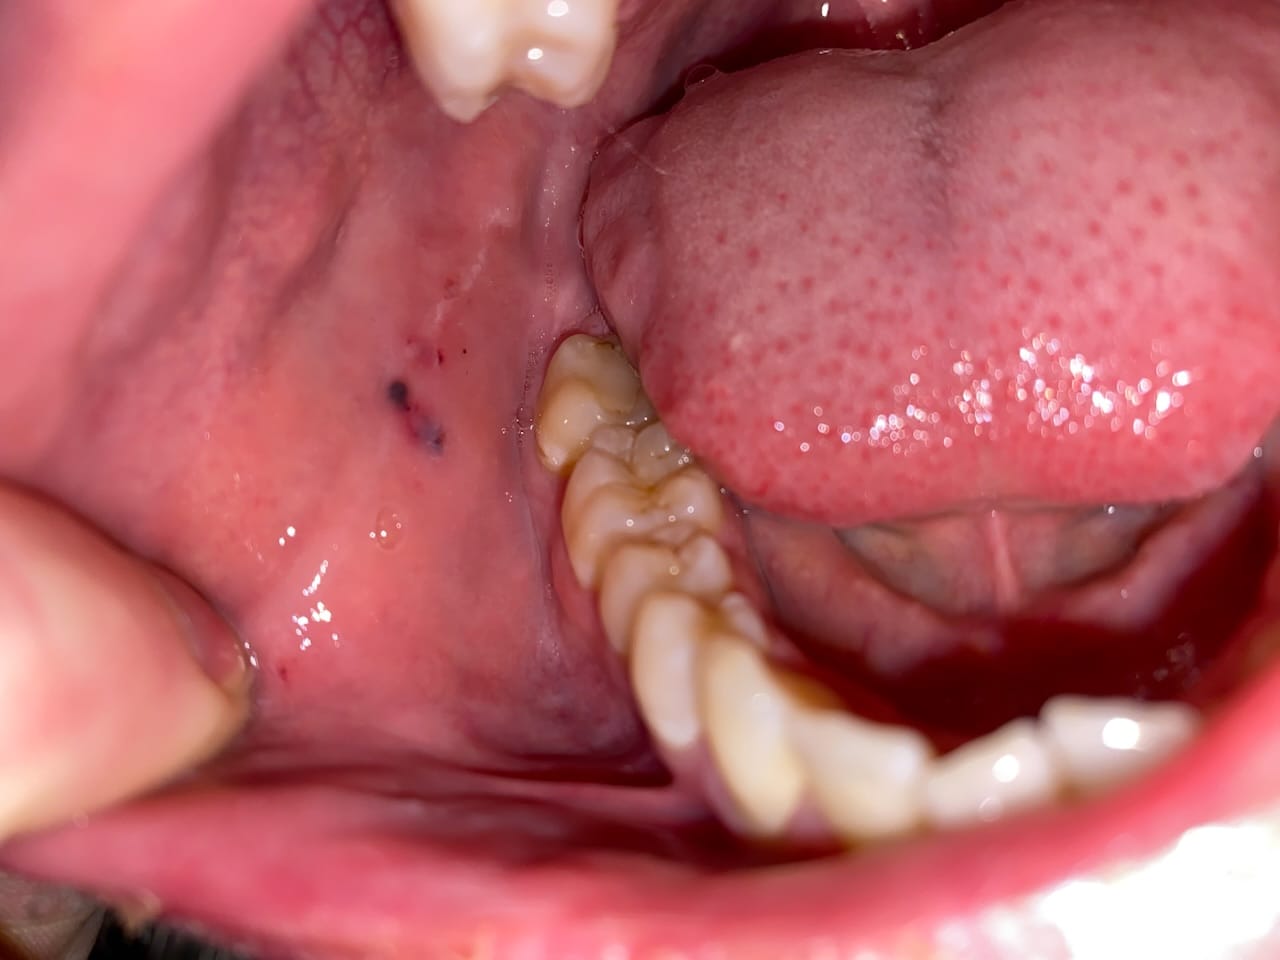

In sommige gevallen kan een slechte uitlijning van de tanden (malocclusie) de oorzaak zijn. Wanneer je tanden niet goed op elkaar passen, kan je wang gemakkelijker tussen je tanden terechtkomen tijdens het kauwen of praten. Raadpleeg een orthodontist als je denkt dat dit de oorzaak is.

- Een verkeerde beet

- Tandheelkundige ingrepen (zoals het plaatsen van een nieuwe kroon of vulling) die tijdelijk de beet veranderen

- TMJ-problemen (Temporomandibulaire Gewrichtsstoornissen), die invloed hebben op de kaakgewrichten en spieren.

Bescherming van de Wang

Als je merkt dat je vaak op dezelfde plek bijt, kun je proberen om de wang te beschermen. Dit kan met:

- Een bitje: Een bitje, vergelijkbaar met wat sporters gebruiken, kan voorkomen dat je op je wang bijt. Overleg met je tandarts over de mogelijkheden.

- Tandheelkundige was: Dit kan je aanbrengen op scherpe randen van je tanden die de wang irriteren.

- Als het wangbijten ernstige pijn veroorzaakt.

- Als er wondjes of zweertjes ontstaan die niet genezen.

- Als je vermoedt dat er sprake is van een slechte uitlijning van de tanden of TMJ-problemen.